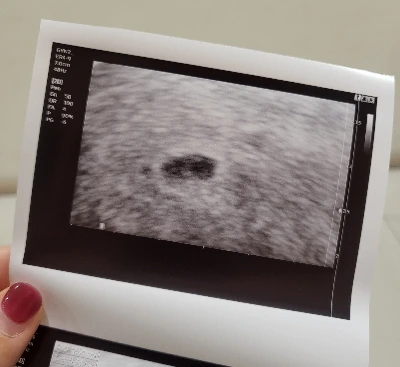

산부인과에서 무사히 아기집의 착공을 확인했다. 자궁외임신이 아니라는 뜻이었고, 현 시점으로서는 무사히 임신이 진행되고 있다는 의미였다. 의사가 출산예정일을 말해주자 뿌앵 하고 눈물이 터졌다. 임신테스트기를 처음 해봤을 때도 눈물은 나지 않았는데. 일주일간 내 자신이 생각한 것 이상으로 마음을 졸인 모양이었다. 질질 흐르는 눈물에 스스로도 당황하고 있으니 의사는 티슈를 뽑아 건네면서 "임신하면 원래 눈물 많아져요. 호르몬 때문에 그래, 호르몬." 했다. 그 말에 눈물이 쏙 들어갔다. 그래, 이것도 임신 증상일지 모른다…